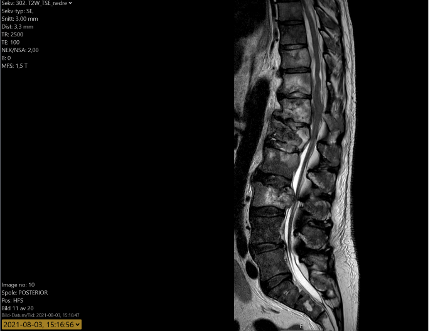

MR ländrygg visar utbredda förändringar med malignt utseende som omfattar alla avbildade kotor (Th12-L5). Expansiva förändringar Th12-L3 som orsakar significant central spinal stenos och rotpåverkan. Patologisk fraktur kan misstänkas i L1.

MR helrygg utförs och visar betydande skelettmetastasering med flertalet metastasangripna kotor i hals- bröst och ländrygg med överväxt in mot spinalkanalen. Ryggkirurg kontaktas för konsoliderande kirurgi men relaterat den spridda metastaseringen bedöms det som utsiktslöst att instrumentera och stabilisera ryggen.

En MR helrygg utförs som visar total regress I bröstryggen, god partiell regress I övre delen av ländryggen med förbättrat utrymme I spinalkanalen jämfört med tidigare undersökning. Progress med forminal rotpåverkan I L1-L2 med vänstersidig övervikt.